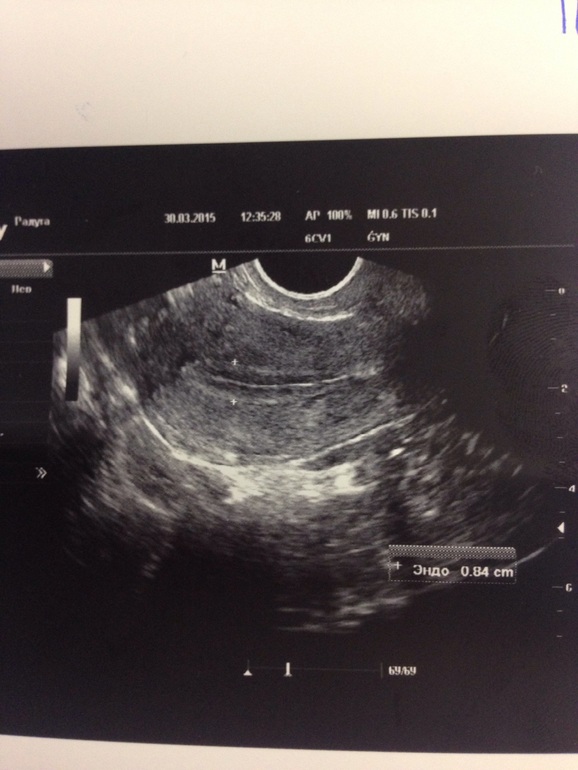

Сегодня 12 день цикла. Сделала УЗИ яичников. В ПЯ домин. фол. 20 мм. Эндометрий трехслойный 8,4.